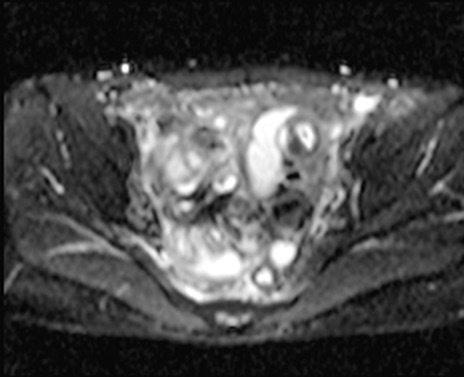

【症例】40歳代女性

【主訴】上下腹部痛

【現病歴】2日目から下腹部痛あり。夜間は痛みで眠れなかった。昨日より上腹部痛と下痢が出現。臥位で痛みは軽快したため、休んでいた。本日になって臥位でも立位でも痛みが強くなってきたため救急要請。

【既往歴】子宮内膜症

【身体所見】部:平坦・軟、左上下腹部に圧痛あり、反跳痛あり。

【データ】WBC 21800、CRP 26.78

MRI(4日後)